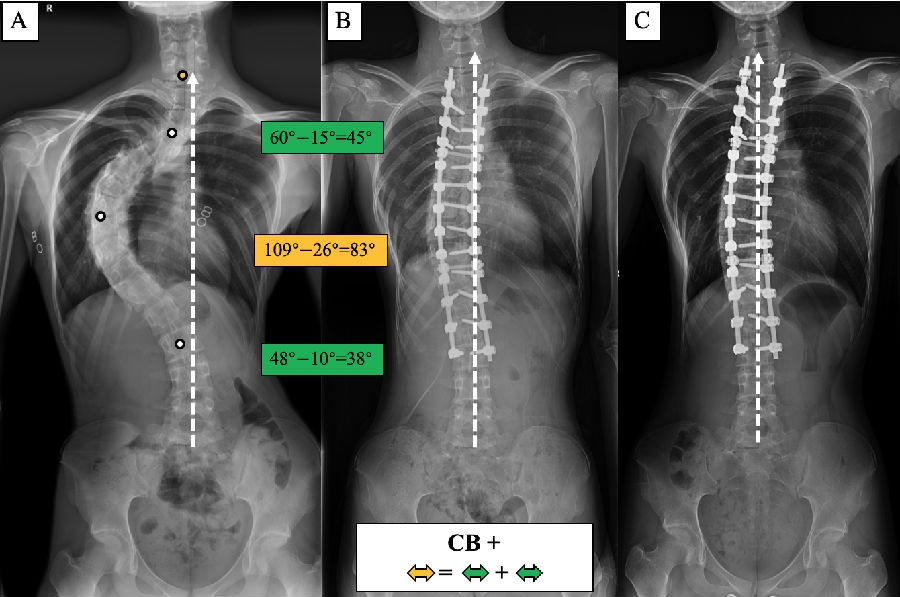

(1) 术前CB-患者:主弯矫正70°,上胸弯及腰弯矫正分别为21°和49°,术后维持平衡状态。

(2) 术前CB+患者:主弯矫正83°,上胸弯及腰弯矫正分别为45°和38°,术后维持平衡状态。

基于以上临床观察,我们提出了脊柱侧凸顶椎位置分布的冠状面平衡修正[7]。首先,根据CBD是否大于2cm,将患者分为冠状面平衡(coronal balanced, CB)和冠状面失平衡(coronal imbalanced, CIB)。然后,根据患者各个弯曲顶椎/椎间隙中心的分布特点,赋予顶椎位置分布修正(-/+),若果各顶椎中心分布在CSVL两侧,则为修正(-),若各顶椎中心分布在CSVL同侧,则为修正(+)(图7)。

图8. 各类型患者的手术矫形策略。